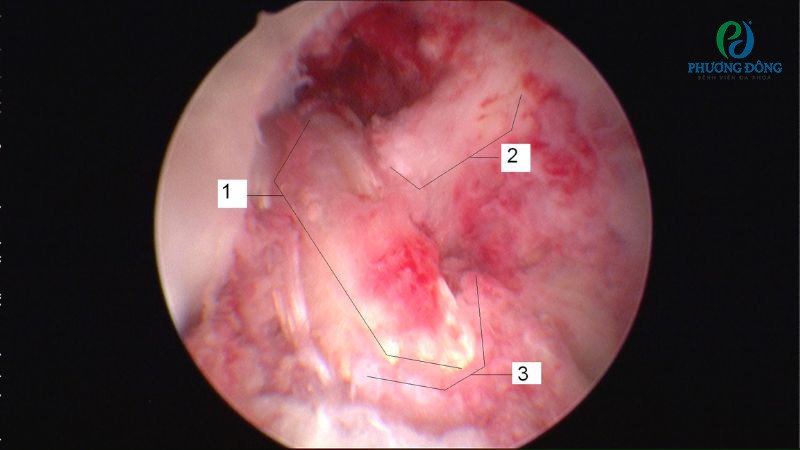

Đối với nội soi khớp gối, bác sĩ chỉ cần rạch một vài đường nhỏ trên da để đưa dụng cụ chuyên dụng vào bên trong. Các thiết bị này giúp bác sĩ quan sát chi tiết, rõ nét cấu trúc cũng như tổn thương bên trong để can thiệp và xử lý tổn thương một cách chính xác.

- Tỷ lệ chính xác cao: Từ camera nội soi, hình ảnh cấu trúc và tổn thương trong khớp gối được phóng đại, giúp việc xử trí và cố định dây chằng mới trở nên dễ dàng, chính xác hơn.

- Bước 5: Tiến hành quan sát tổn thương dây chằng chéo trước, can thiệp thông qua hình ảnh được phóng đại trên màn hình lớn.